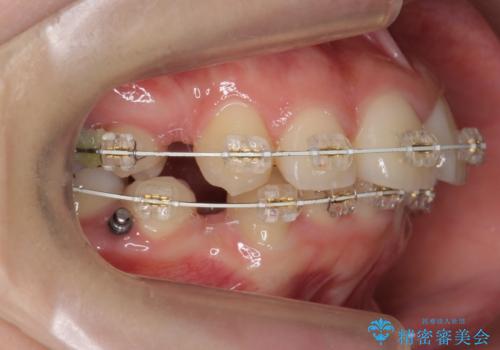

- 矯正装置

- 審美装置

- 治療期間

- 2年1ヶ月

口元を下げたいとのことで、歯を抜いてワイヤー矯正を行いました。

上下左右の小臼歯を抜歯しています。